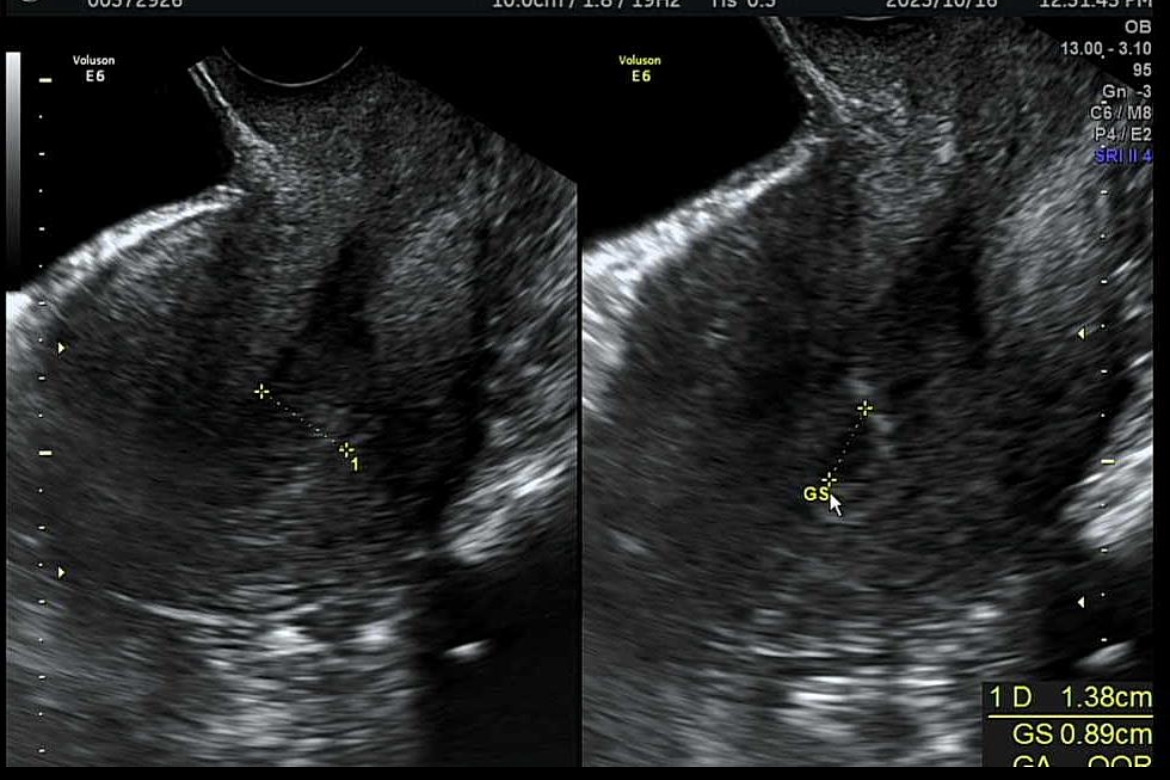

2023년 10월. 콩알만 하게 초음파에 보이는 아기의 심장소리를 처음 들었다. 살면서 느껴보지 못한 몽글몽글한 감정이 올라왔다. 가족들에게도 소식을 전했다. 이 작은 5mm의 존재가 우리 부부를 포함한 많은 이들에게 행복감을 안겨준다는 것 자체가 벅찼다.